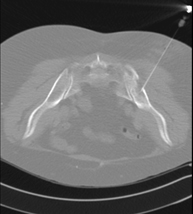

- Biòpsia òssia guiada per TC Consisteix en obtenir una mostra de teixit d'una determinada lesió òssia. En ocasions es realitza sota sedació, amb l'ajuda de l'equip d'anestèsia. S'utilitzen agulles que permeten l'obtenció d'un cilindre de la lesió que s'ha d'estudiar, que s'enviarà a Anatomia Patològica per a la seva anàlisi histològica. Tot el procediment es realitza controlat amb imatges obtingudes per Tomografia Computaritzada (TC). Després de la prova, el pacient resta hospitalitzat per controlar la seva evolució. És necessari que porti les proves de coagulació abans de la punció. Consisteix en obtenir una mostra de teixit d'una determinada lesió òssia. En ocasions es realitza sota sedació, amb l'ajuda de l'equip d'anestèsia. S'utilitzen agulles que permeten l'obtenció d'un cilindre de la lesió que s'ha d'estudiar, que s'enviarà a Anatomia Patològica per a la seva anàlisi histològica. Tot el procediment es realitza controlat amb imatges obtingudes per Tomografia Computaritzada (TC). Després de la prova, el pacient resta hospitalitzat per controlar la seva evolució. És necessari que porti les proves de coagulació abans de la punció.

- Biòpsia òssia guiada per TC Exploració invasiva que permet obtenir mostres de teixit ossi, principalment procedent de tumoracions. El TC és utilitzat per seleccionar la zona de punció i guiar les agulles de biòpsia fins la tumoració. S'aplica anestèsia local i, ocasionalment, sedació. La durada del procediment depèn de la seva dificultat tècnica d'aquest. Exploració invasiva que permet obtenir mostres de teixit ossi, principalment procedent de tumoracions. El TC és utilitzat per seleccionar la zona de punció i guiar les agulles de biòpsia fins la tumoració. S'aplica anestèsia local i, ocasionalment, sedació. La durada del procediment depèn de la seva dificultat tècnica d'aquest.